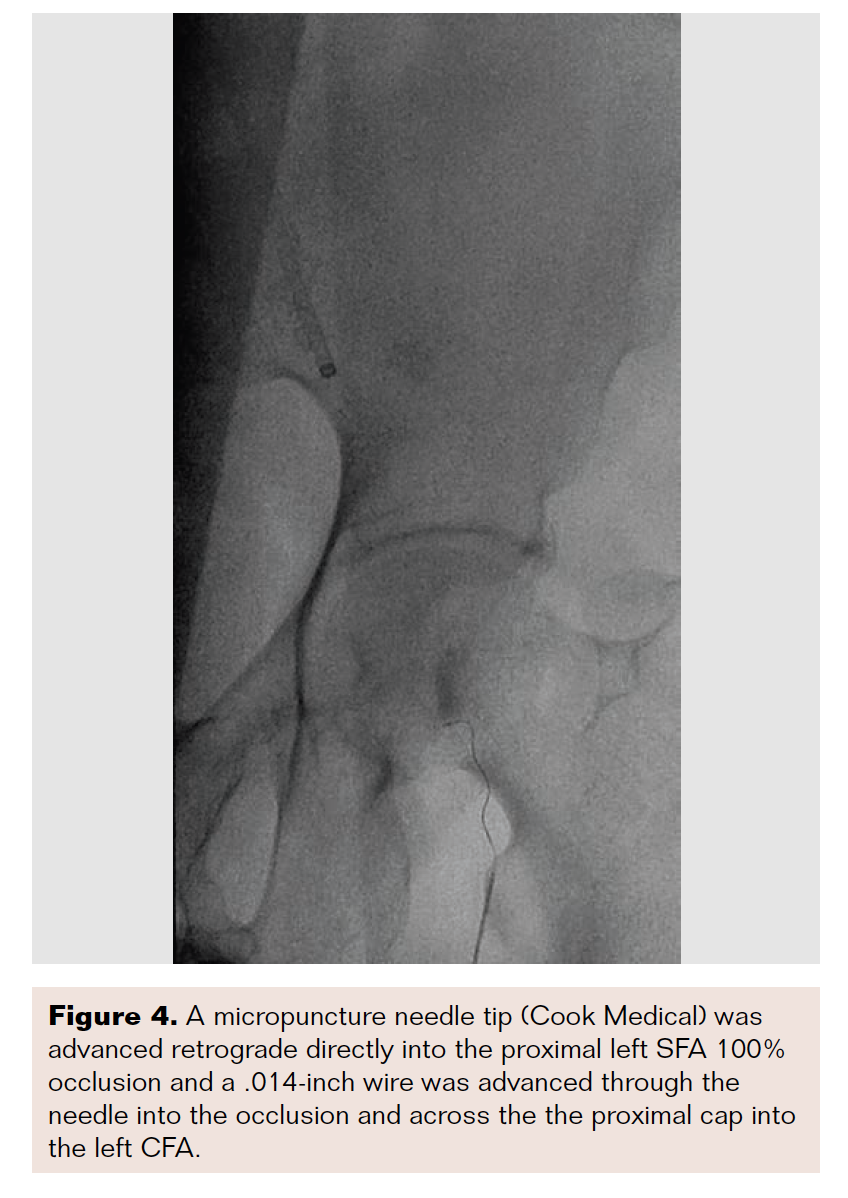

A 5 French (Fr) 11 cm sheath that was initially placed in the right CFA was exchanged over a wire for a 7 × 45 cm sheath that was advanced “up and over” and placed antegrade at the ipsilateral left CFA. Brief unsuccessful attempts were made with .018-inch and .014-inch wires to cross the SFA given the calcific proximal “flush” occlusion, with wires favoring the open profunda artery (Figure 2A). Using extravascular ultrasound visualization, a micropuncture needle tip (Cook Medical) was advanced retrograde directly into the proximal left SFA 100% occlusion, and a .014-inch wire was advanced through a needle into the occlusion and across the proximal cap into the left

CFA (Figures 3, 4, and 5A).

Pedal access techniques have improved the success of intervening in these types of SFA occlusions, as these caps can be approached retrogradely.5 Despite this improvement, the pedal approach does not guarantee that a retrograde wire can be maintained intraluminally, or even if luminal, that the CFA can be reentered. Approaching the proximal SFA occlusion directly under extravascular ultrasound guidance retrograde with a micropuncture needle (Figures 3, 4, and 5A) allows for the visualization of the needle tip well enough to ensure that the wire is intraluminal and also provides great support to advance both 0.014-inch and 0.018-inch wires, both hydrophilic tip and heavy gram wires, with excellent control. The wire can then be advanced into the previously placed antegrade sheath, and a microcatheter can be advanced antegrade past the proximal cap and worked via the standard access (Figures 5B-C).